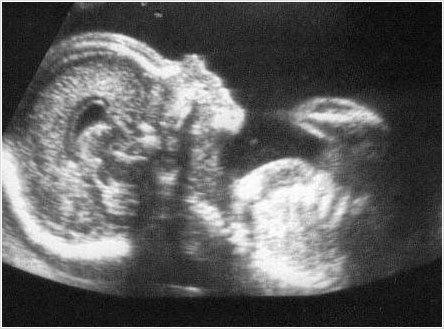

-Biometría y estimación de peso fetal. Asignación de percentil según curva OMS -Evaluación Doppler materno-fetal -Pesquisa Restricción Crecimiento Fetal -Reevaluación anatomía fetal para detección de malformaciones congénitas de aparición tardía -Placenta: localización y aspecto -Volumen de líquido amniótico